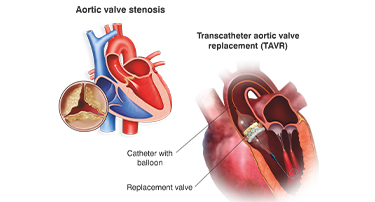

Modern Cardiac Care: The Role of TAVR in Structural Heart Disease Treatment

Nature is just amazing. Look at the amazing things. Just look around, or better yet, look within yourself. Your heart, for example, is a true marvel, working tirelessly, 24/7, never taking even a nap.

Innovative Heart Valve Solutions That Avoid Open-Heart Surgery

For decades, open-heart surgery was the sole method for repairing or replacing a defective heart valve. Although effective, the old method is marked by giant incisions, extended recovery periods, and jeopardy to elderly or high-risk patients.

TAVI Vs. Open-Heart Surgery: Which Is The Right Choice For You?

For heart valve replacement, patients usually have two primary choices: Transcatheter Aortic Valve Implantation (TAVI) and open-heart surgery. Both involve replacing a faulty aortic valve, but they are very different in approach, recovery period, and applicability to various patient populations. Knowing the main differences, advantages, disadvantages, and success rates can assist you in making an informed choice.

Who Is The Ideal Candidate For TAVI? Understanding Eligibility & Benefits

Transcatheter Aortic Valve Implantation (TAVI) has revolutionized the treatment of severe aortic stenosis, especially for patients who are high-risk candidates for traditional open-heart surgery. This minimally invasive procedure offers a lifeline to many, but determining who stands to benefit the most is crucial.